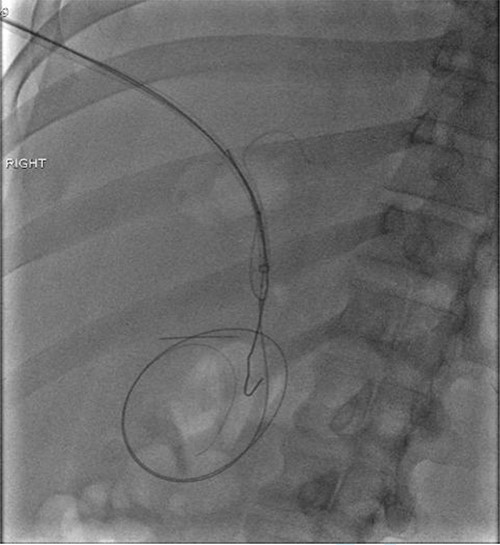

The patient underwent left hepatic abscess drainage and fluoroscopic-guided foreign body retrieval of intrahepatic foreign body. Through an image guided intercostal approach, an 0.035 inch guidewire was coiled within the hepatic abscess and a vascular sheath was introduced. The hepatic end of the paper clip was able to be snared, but could not be completely removed due to lack of traction. The snare was able to guide the end of the paperclip into the sheath where a high pressure non-compliant balloon (Conquest) was the inserted over an 0.035 inch stiff Glidewire and inflated in the sheath adjacent to end of the paperclip to wedge the paperclip into the vascular sheath, and under fluoroscopic guidance, the inflated Conquest balloon, paperclip and vascular sheath were successfully removed as a unit (Figs 4 and 5). A drain was left in the hepatic collection. The two small extraluminal foreign bodies were left in place.

Fluoroscopic image obtained intraoperatively demonstrating removal of the metallic foreign body